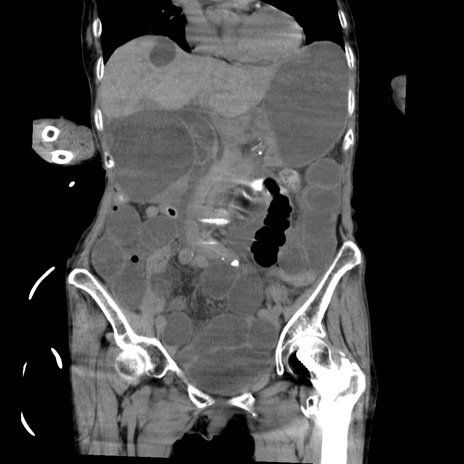

症例27(冠状断像)

【症例】80歳代女性

【主訴】嘔吐、腹痛

【現病歴】数時間前より嘔吐あり。心窩部痛出現し、徐々に右下腹痛あり。その後も数回嘔吐あり救急搬送となる。

【既往歴】左大腿骨頚部骨折手術

【身体所見】腹部は膨隆しているが軟らかく圧痛なし。腸雑音はやや亢進。

【データ】WBC 12000、CRP 19.05